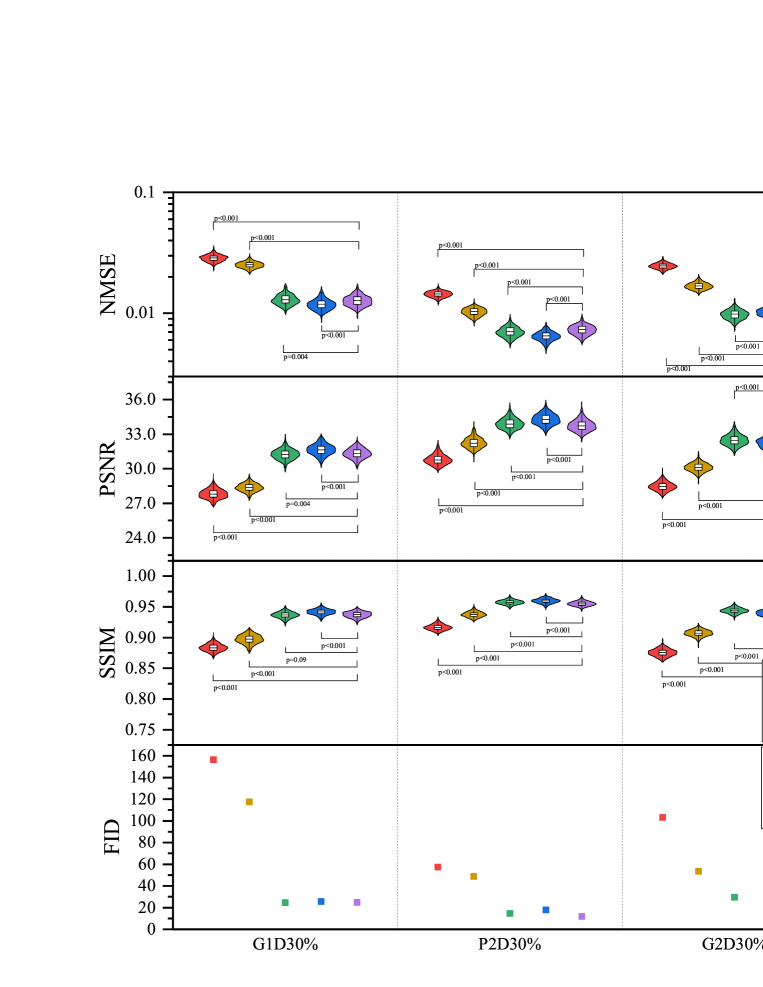

The testing result are shown in Fig. 7 and Fig. 8. Experimental results exhibit the same trend under all the different downsampling trajectories. The proposed method provides significant advantages for low downsampling percentage (high acceleration factor), with correspondingly significantly improved reconstruction quality.